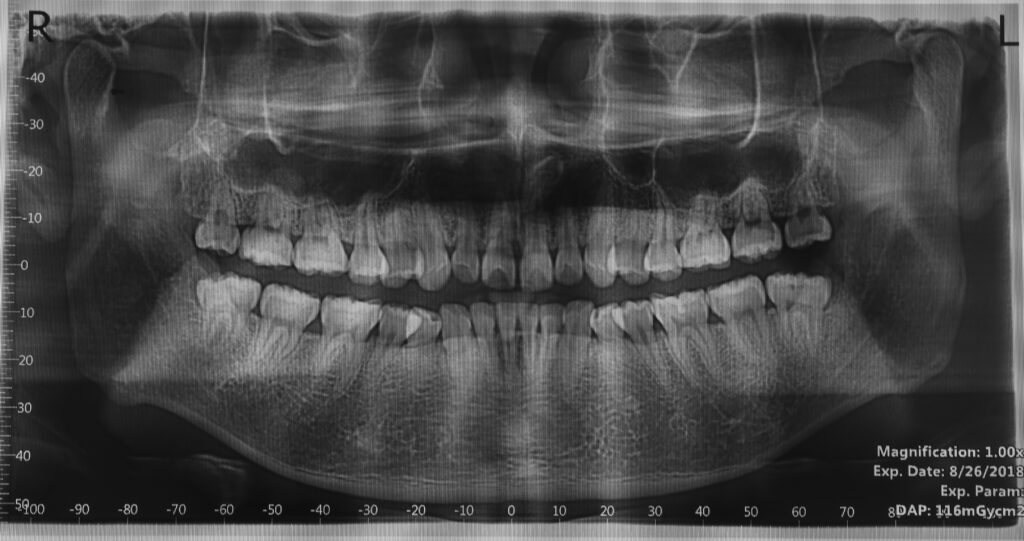

Tình trạng khi tiếp nhận điều trị: bệnh nhân còn khoảng nhổ răng, khớp cắn sâu, nâng khớp hàm dưới trên 4mm, đường giữa hàm dưới lệch phải 2mm so với đường giữa hàm trên.